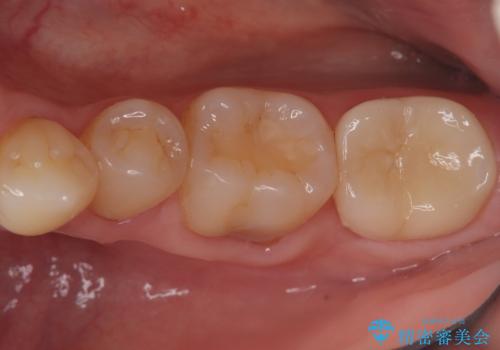

汚れの溜まりやすい銀歯を精度の高いセラミック治療で改善